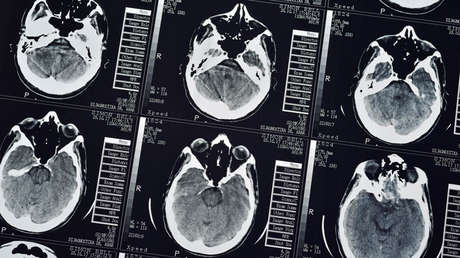

El aislamiento social prolongado y la monotonía ambiental podrían impedir la generación de nuevas neuronas y causar la reducción de algunas zonas del cerebro en los humanos, según un nuevo estudio.

Un informe publicado en la revista The New England Journal of Medicine revela los resultados del estudio efectuado en nueve miembros de una expedición antártica. Entre los cambios más reseñables que experimentaron los científicos polares destacan: la reducción del giro dentado del hipocampo, una de las pocas zonas cerebrales asociada con la neurogénesis adulta (nacimiento de nuevas neuronas) en muchos mamíferos; así como los niveles del factor neurotrófico derivado del cerebro, proteína vinculada al crecimiento nervioso.

Los investigadores establecieron que en los 14 meses el volumen del hipocampo cambió en todos los participantes. El grupo de control mostró un ligero crecimiento en promedio, mientras que los exploradores polares experimentaron una reducción. La zona del hipocampo que más sufrió fue el giro dentado, que se contrajo un 7,2%. Su reducción se correlacionó con un peor rendimiento en tests de atención selectiva y orientación espacial, pero no con otras capacidades cognitivas.